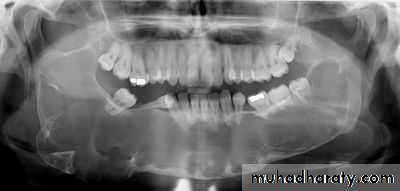

4. Keratocysts:Many follicular and dentigerous cysts contain keratinizing material and are known as keratocysts. These cysts differ from other odontogenic cysts in their microscopic appearance and clinical behavior. Keratocysts in crease in size principally by a process of epithelial cell multiplication and have a greater tendency toward recurrence.